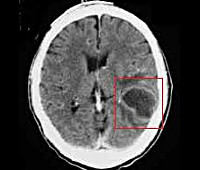

- КТ или МРТ головного мозга. Исследования дают возможность четко визуализировать локализацию абсцессов или очагового энцефалита, определить их размеры, выявить перифокальный отек, дислокацию и деформацию желудочков мозга. Контрастные методики показаны при подозрении на тромбоз кавернозного или сигмовидного синуса.

- Абсцесс головного мозга, мозжечка – патологические полости, ограниченные пиогенной мембраной и заполненные гнойными массами. Типичное расположение при отогенном происхождении – височная доля, мозжечок.

- Компьютерная томография и ядерно-магнитный резонанс.